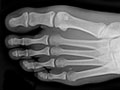

Extremity X-Ray

An extremity X-ray is a picture of your hand, wrist, arm, foot, ankle, knee, hip, or leg. It is done to see whether a bone has been fractured or a joint dislocated. It is also used to check for an injury or damage from conditions such as an infection, arthritis, bone growths (tumors), or other bone diseases, such as osteoporosis.